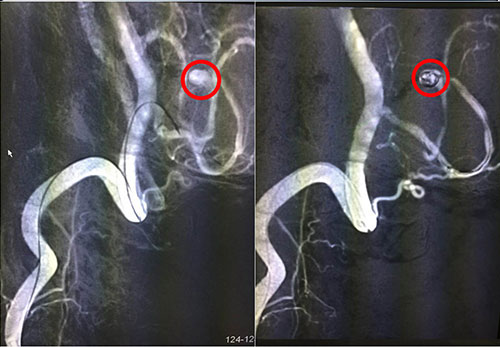

我院神经外科专家潘仁龙等多次与沪上知名神经外科专家联合会诊,讨论患者病情及治疗方案,认为目前诊断明确,患者病情患者具备手术指征,手术方式有:开颅动脉瘤夹闭术和动脉瘤介入栓塞术。由于患者左脑后下动脉瘤体在血管远端,接近脑干边上,手术难度较大,风险极大,在术中、术后均可能发生出血而导致死亡可能。考虑到患者情况高危,又开颅动脉瘤夹闭术相较于介入栓塞术创伤大,风险大,经征求家属意见后,决定为患者全麻下实施左小脑后下动脉瘤介入栓塞术,由我院神经外科专家潘仁龙主任主刀,并特邀华山医院专家协同技术指导。

红圈内为术中介入微导管微弹簧

脑动脉瘤的介入治疗,最常用的是用弹簧圈栓塞动脉瘤。简单地说,就是从大腿根部的股动脉插管,将一根很细的微导管通过动脉官腔内直接插到脑动脉瘤内,再通过这根很细的微导管送入一段一段盘旋的微弹簧圈,逐步将动脉瘤腔内填满,诱发血栓形成后,使动脉瘤腔没有血流通过,而正常的脑动脉保留通畅,从而达到治疗的目的。12月6日手术进行,术程顺利,患者安返ICU进行术后监护。